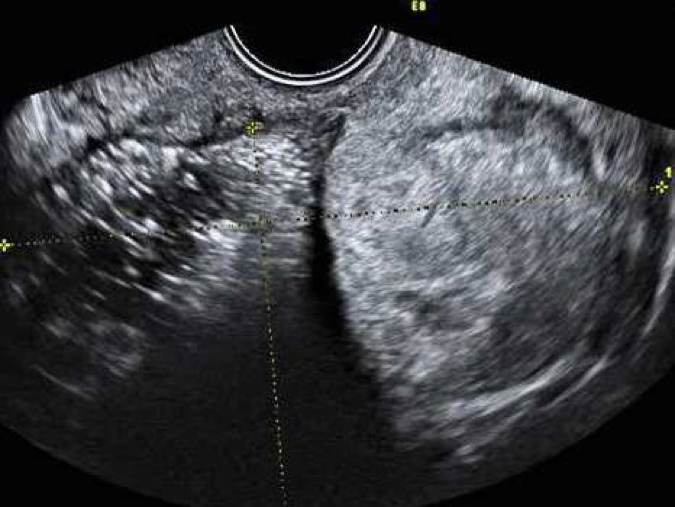

Dysgerminom är en av de vanligaste typerna av groddcellstumör och förekommer ofta hos unga kvinnor; 80 % är yngre än 30 år. Tumörformen är sällsynt hos kvinnor som genomgått menopaus. AFP- och hCG kan vara förhöjda liksom även LD. Bilaterala tumörer ses hos 10–15 % av kvinnorna. Tumörerna är solida, lobulerade, välvaskulariserade och ofta stora (10–15 cm) vid diagnos. Se bild 1.

Bild 1. Snabbväxande dysgerminom hos 22-årig gravid kvinna med förhöjt S-LD.